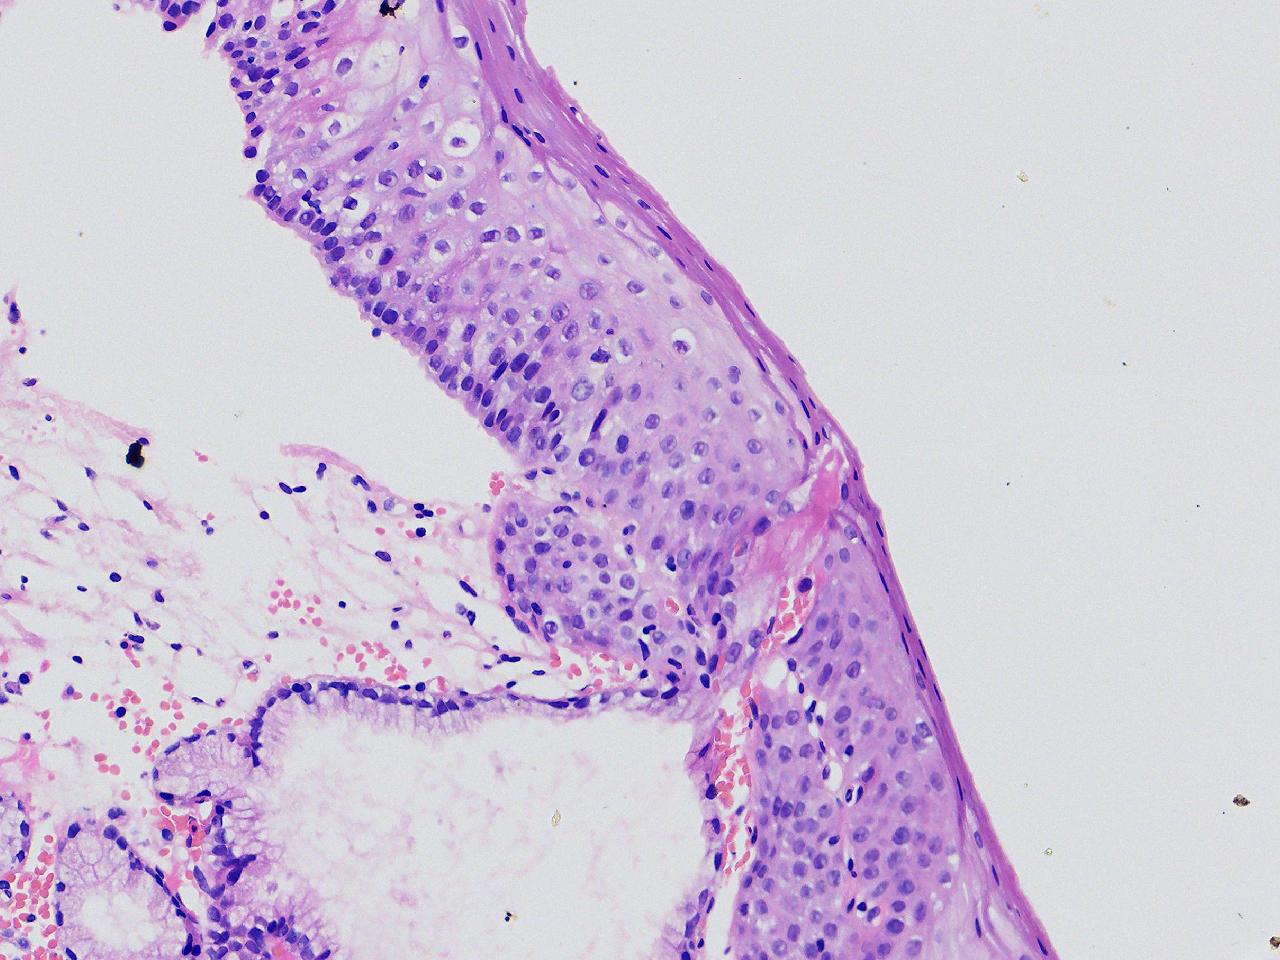

女,38岁,食管距门齿38cm处见一扁平隆起,表面粗糙,活检1块,质软,弹性可。

食管活检

灰白色不整形软组织1块,直径0.2厘米。

结合取材部位排除Barrett食管

粘膜慢性炎。

Barrett食管,粘膜慢性炎。